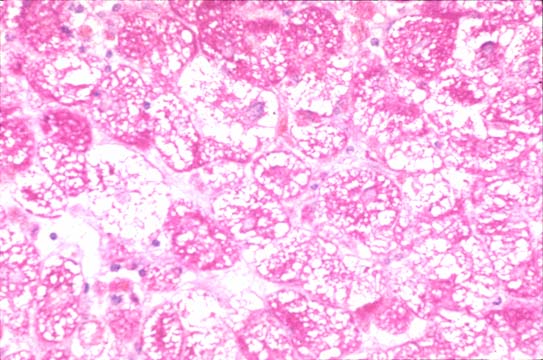

Fig 37 - Fat in microvesicles

in acute fatty liver

of pregnancy.